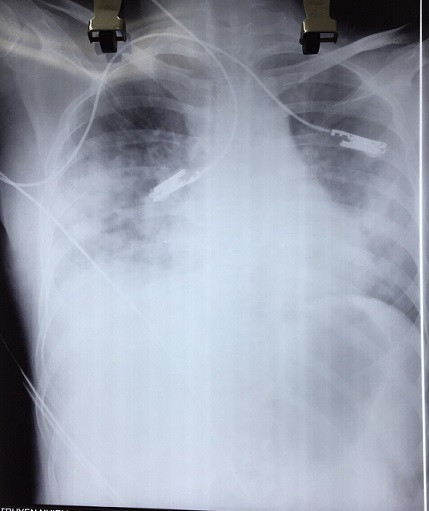

Hình ảnh chụp X-quang viêm phổi của bệnh nhân

Bệnh nhân B.T.M.H (27 tuổi, ở Sơn Dương, Tuyên Quang) có tiền sử lupus ban đỏ hệ thống đã 7 năm nay và hiện đang điều trị nội trú tại Trung tâm Dị ứng - Miễn dịch Lâm sàng, Bệnh viện Bạch Mai. Bệnh nhân kèm thêm mắc hội chứng Raynaud đã cắt 4 đốt ngón tay hai bên, hoại tử ngón chân 4,5 trái chưa cắt. Tuy nhiên, ngày 1/3/2018, bệnh nhân được chuyển sang Khoa Truyền nhiễm với triệu chứng sốt ngày thứ 2 và xuất hiện ban phỏng nước rải rác vùng cẳng tay, thân mình. Chỉ một ngày sau, bệnh nhân khó thở, gắng sức, ho ít, thể trạng suy kiệt… Phim chụp XQ và các xét nghiệm cho thấy bệnh nhân bị biến chứng viêm phổi nặng sau thủy đậu, trên nền lupus ban đỏ hệ thống/hoại tử đầu chi. Hiện bệnh nhân đang được điều trị tích cực, phải thở ô-xy song tiên lượng rất dè dặt.